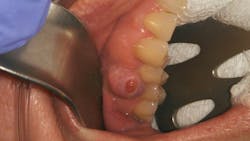

Clinical assessment revealed a 6 mm pink, raised, firm mass of osseous tissue measuring 12x12 mm. It was not tender to palpation and did not bleed easily when manipulated (figures 1 and 2). Radiographic assessment was within normal limits (figure 3).